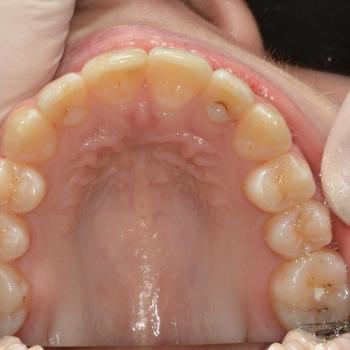

Eszter és édesanyja az iskolai fogorvosuk javaslatára kerestek fel, mert a kolléga, az esztétikai problémát okozó torlódás mellett, Angle II. osztályú funkciós eltérést is tapasztalt. Szerencsére ezeken felül egyéb eltérésre a konzultáció alkalmával sem derült fény.

Eszter a kezelés megkezdésekor headgear típusú fogszabályozó készüléket kapott annak érdekében, hogy a felső nagyőrlőket hátrafelé mozgassuk, illetve, hogy a keletkező rést felhasználjuk a kisőrlők és a szemfogak hátramozdítására is. Az így felszabadult hely az Eszter által választott hagyományos fém fogszabályozó segítségével felhasználható volt a metszőfogak elrendezéséhez, azok túlzott előredőlése nélkül.

A kezelés eredményeként minden kiindulási problémát sikerült megoldani és egy esztétikailag és funkcionálisan is szép mosolyt létrehoznunk.